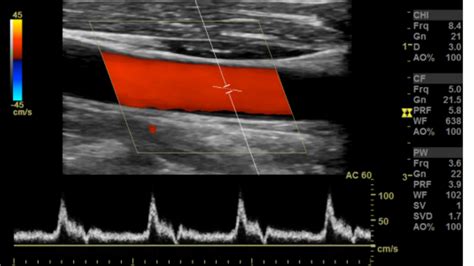

Ultrasound (Doppler) Visualizes blood flow through the vessels and identifies blockages.